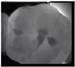

| 0 | Sound![]() | No shadow![]() | No radiolucency![]() |

| 1 Early | First Visual change in enamel![]() | Thin grey shadow into enamel![]() | Radiolucency in outer half of enamel![]() |

| 2 Distinct | Distinct Visual change in enamel ![]() | Wide grey shadow into enamel![]() | Radiolucency in inner half if enamel +/- Enamel dentin junction![]() |

| 3 Distinct | Localized enamel breakdown![]() | Shadow less than 2mm in dentine![]() | Radiolucency limited to outer 1/3 of dentine![]() |

| 4 Distinct | Underlying dentinal shadow![]() | Shadow more than 2 mm in dentine![]() | Radiolucency passed 1/3 of dentine![]() |